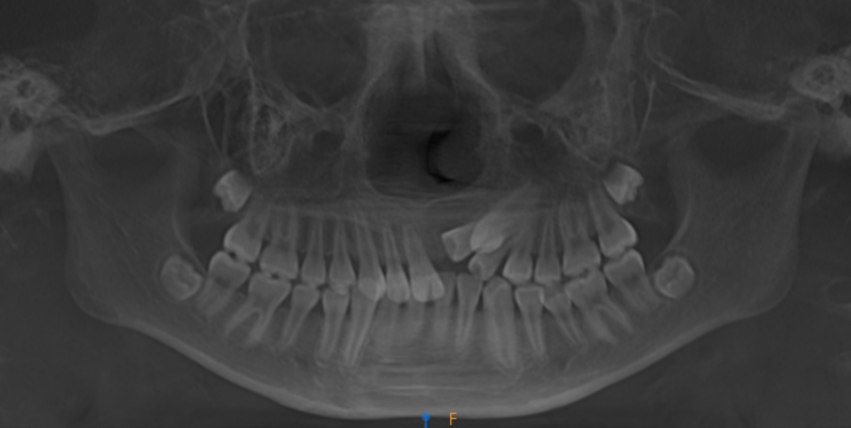

口腔正畸科副主任医师尹苗接诊后进行了细致检查,发现康康口内乳牙已全部脱落,进入恒牙列期,后续替换的乳牙均正常萌出,但左上颌区本应更早萌出的 3 颗前牙却「缺席」。通过锥形束 CT(CBCT)检查,结果显示这 3 颗恒牙并非未发育,而是全部位置异常,牙冠呈近中倾斜阻生状态,其中左上门牙完全埋伏于颌骨内。

针对康康的情况,尹苗副主任医师团队制定了治疗方案:首先通过 CBCT 精准定位埋伏牙位置、角度及与邻牙关系;随后在可见牙列上安装托槽弓丝,以弹性链或钢丝连接并施加轻柔持续的牵引力,激活牙周反应,促使牙齿沿预设轨道移动至正常位置。牙齿归位后需经历稳定期,拆除矫治器后还需佩戴保持器防止复位。